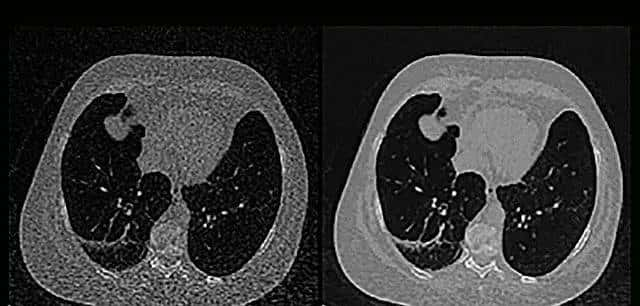

2.图片降噪

原图存在噪点是不可避免的,噪点会导致细节变得模糊,影响轮廓和边界的判断,简单的情况可通过调节直方图均衡化解析参数来减少噪点,实际应用时降噪是超级复杂的,因每家医院的设备厂商、型号不同且设备寿命、保养情况不同,照片质量差异超级大,这个过程也可以训练单独的CNN模型来处理,实际效果类似如下: